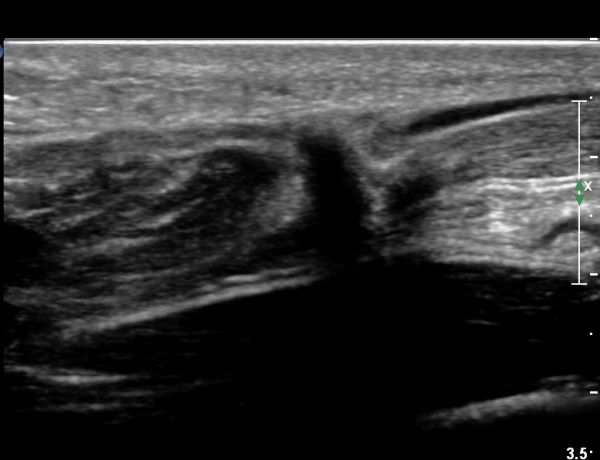

ºñº¹±Ù Á¾´Ü¸é°Ë»ç¿¡¼ ƯÀÌ ¼Ò°ßÀ» º¸ÀÌÁö ¾ÊÀ½(»çÁø 1).

¾ÆÅ³·¹½º°Ç Á¾´Ü¸é°Ë»ç¿¡¼ ¾ÆÅ³·¹½º°Ç Àú¿¡ÄÚ ºÎÁ¾, ¿¬°á¼º ¼Ò½Ç, °ÇÁÖÀ§ ¼ö¾×Àú·ù ¼Ò°ßÀ» º¸ÀÓ(»çÁø 2, 3, 4, 5).